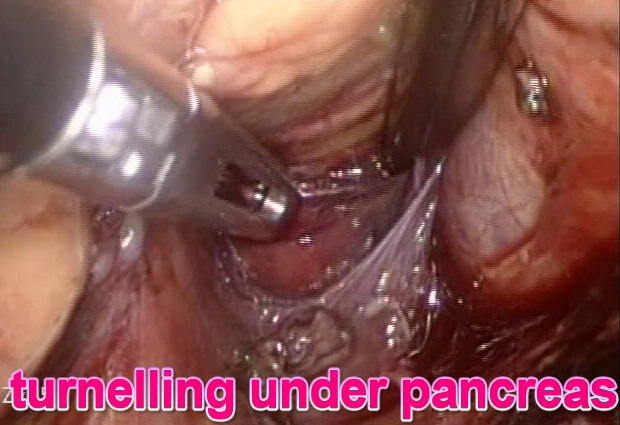

- Distal pancreatectomy (for removal of pancreas tumor)

- Whipple operation (for removal of pancreas cancer)